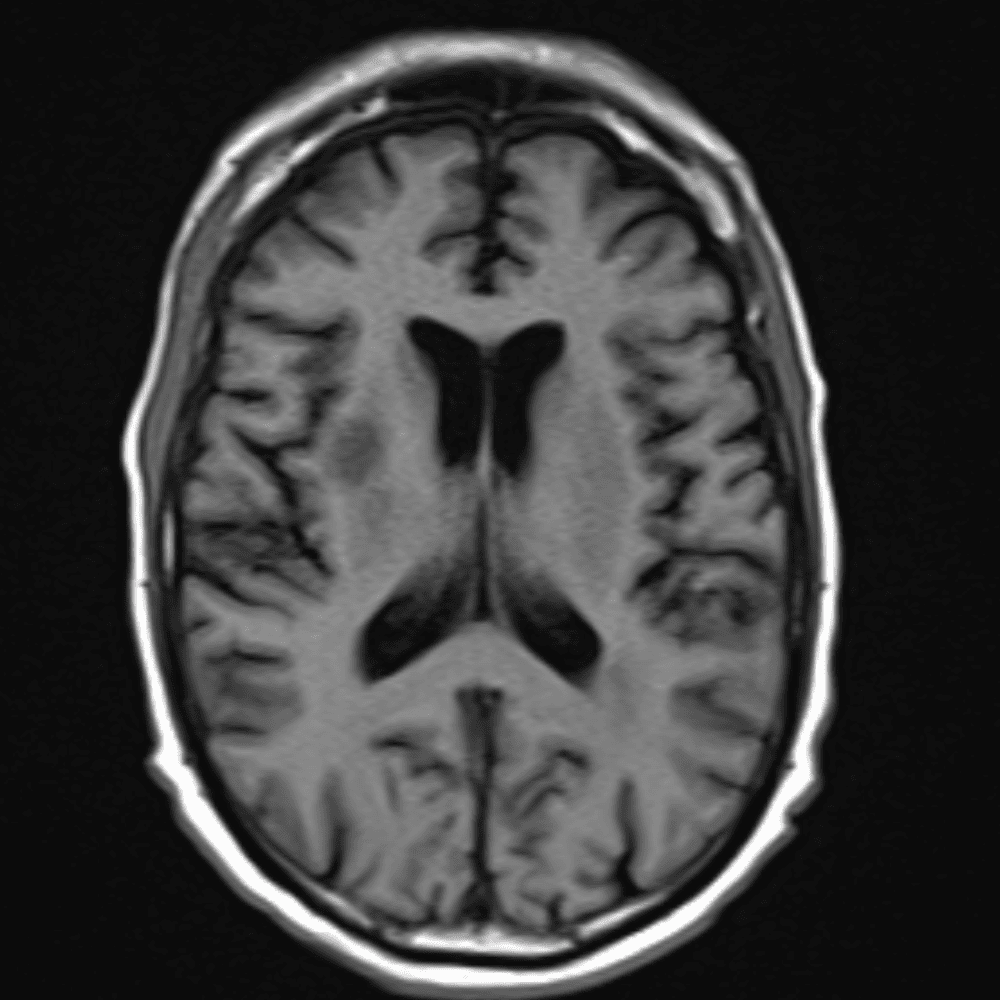

๋‹น์ง ์‹œ ํ”ํžˆ ๋ณผ ์ˆ˜ ์žˆ๋Š” ์‚ฌ๋ก€์˜ ์ „ํ˜•์ ์ธ ์˜ˆ๋ฅผ ํฌํ•จํ•ฉ๋‹ˆ๋‹ค.

39 ์‚ฌ๋ก€

์—ฐ์Šต

๋ฏธ๋ฌ˜ํ•˜๊ฑฐ๋‚˜ ์–ด๋ ค์šด ์‚ฌ๋ก€์™€ ์ผ๋ถ€ ์ •์ƒ ์‚ฌ๋ก€๋ฅผ ํฌํ•จํ•˜์—ฌ ๋‹น์ง์„ ์‹œ๋ฎฌ๋ ˆ์ด์…˜ํ•ฉ๋‹ˆ๋‹ค.

50 ์‚ฌ๋ก€